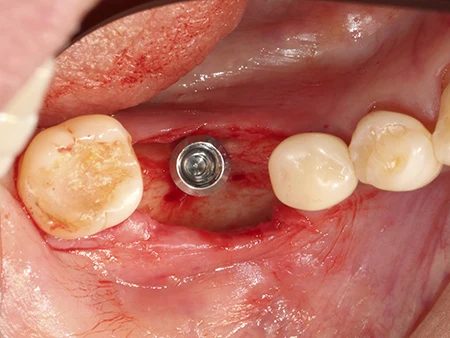

インプラントを埋入した状態。骨の外側からインプラントの一部がはみ出しています。